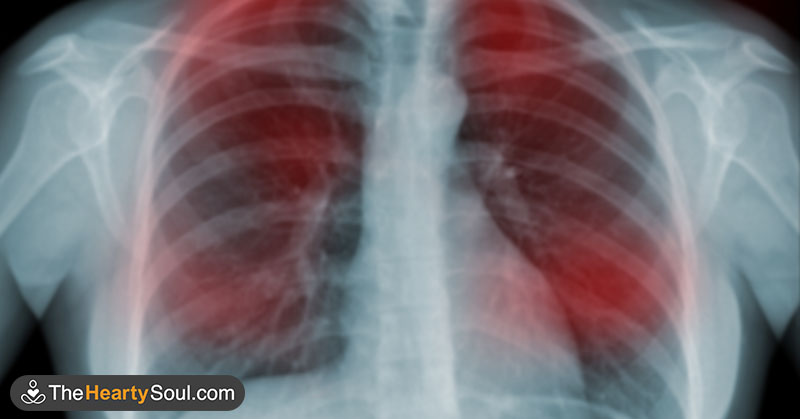

8) Tuse ori răgușeală prelungită – mai mult de 3–4 săptămâni, cu sau fără striuri de sânge.

20) Lipsă de aer la efort și tuse cu episoade respiratorii repetate – scade toleranța la efort, apar infecții pulmonare recurente sau dureri toracice neexplicate.